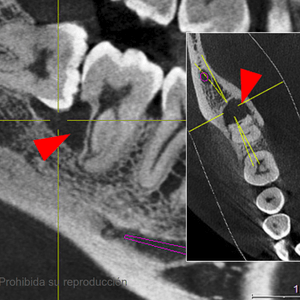

Scanner Cone-Beam CT de última generación

Panorámicas, teleradiografias y CBCT con el sensor más moderno, preciso y de baja dosis.

2Diagnóstico por especialista

Cada caso es único. Informe completo en el menor tiempo posible.